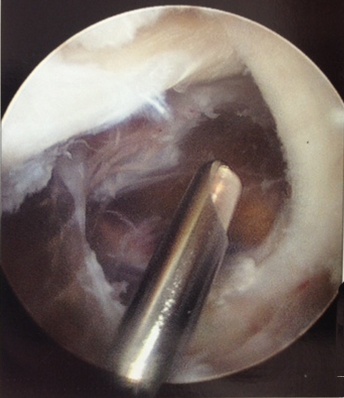

Arthroscopic resection of a popliteal cyst

From the collection of Dr John Kelly IV; used with permission

From the collection of Dr John D. Kelly IV; used with permission